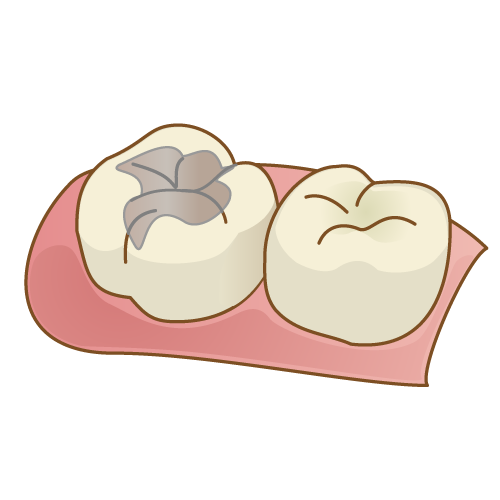

⑥ 前回詰めた綿花の状態を確認して、良い状態なら、「根管充填剤」(マスターポイント・アクセサリーポイント)というお薬を、余分な空間がないように根っこに詰めます。

⑥ 前回詰めた綿花の状態を確認して、良い状態なら、「根管充填剤」(マスターポイント・アクセサリーポイント)というお薬を、余分な空間がないように根っこに詰めます。 Q1.痛みはありますか?

Q1.痛みはありますか? ② 次に、「根管長測定器」という機械を使い、根っこの長さを正確に測ります。

② 次に、「根管長測定器」という機械を使い、根っこの長さを正確に測ります。

⑤ 次に、仮詰めをします。

⑤ 次に、仮詰めをします。 虫歯が神経まで達して炎症を起こしているので、人によってはズキズキとした痛みを感じる方もいます(>_<)

虫歯が神経まで達して炎症を起こしているので、人によってはズキズキとした痛みを感じる方もいます(>_<)